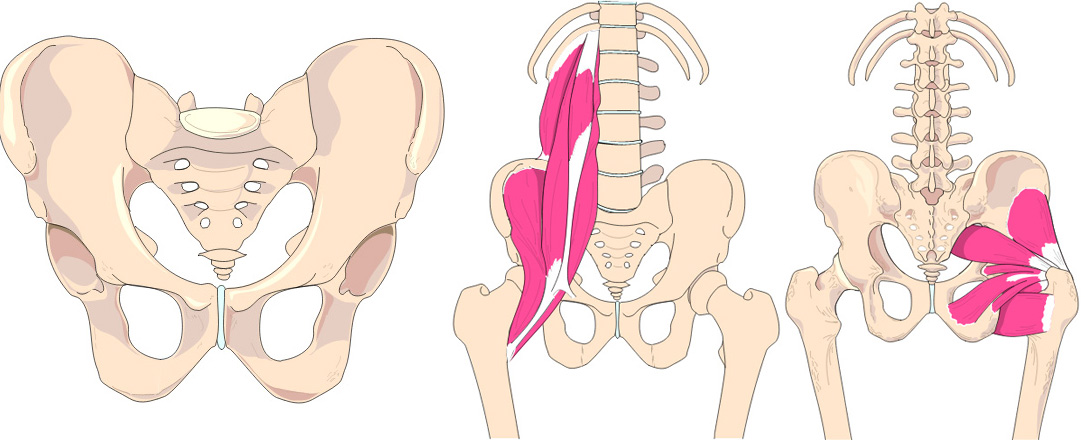

Der Körper besteht aus drei Hauptteilen:

Becken als Mittelebene, Oberkörper wird auf die Mittelebene abgestützt, die Beine mit den Füssen werden am Becken aufgehängt.

Ist die Mittelebene nicht waagrecht und senkrecht in der Mitte ausgerichtet, kann weder der Oberkörper noch die Beine ausgeglichen abgestützt oder aufgehängt werden.

2. Auf einer schiefen Beckenebene kann der Oberkörper nicht senkrecht abgestützt werden. Folglich führt dies zu einer einseitigen Muskelspannungslinie, damit ein aufrechtes stehen und gehen möglich ist. |

1. Verschiebt sich das Becken zur Seite, oder verdreht es dasselbe, führt dies automatisch zu einer Beckenhöhenabweichung, die dann irrtümlich als Beinlängen-Unterschied bebildert und vermessen wird. |

3. Durch den Beckenschiefstand und der einseitigen Oberkörper-spannung weicht zudem das Becken auch noch seitlich aus. Vielmals wird dieser Beinstellungs-Veränderung mit auswärts drehen der Bein-Fussachse oder mit einem Knickfuss dagegen gehalten. Somit wird dem einseitigen steileren Anstellungswinkel der Veränderten Hüftkugelübertragung dagegen gehalten. |

4. Becken Vergleich mit einem Gleichschenkligen Dreieck. |

Diese seitliche Verschiebung hat zur Folge, dass der Schenkel mit dem vergrösserten Winkel zum Becken nach innen drückt. Die Gegenseite drückt durch den kleineren Winkel die Hüftkugel noch oben. Dem wird dann vielmals durch auswärtsdrehen dieses Fusses dagegengehalten. | Beinstellungsveränderung Durch seitliche Hüftverschiebung, hier auf der Abbildung Mitte zu sehen ist, erfolgt eine scheinbare wie auch messbare längen Abweichungen. Grund dafür ist die seitliche Beckenverschiebung die zu einer Schenkel Winkel Veränderung zum Becken führt und somit den scheinbare längen Unterschied verursacht. |

5. Bei der Abbildung kann man ersehen, dass wir auf den Beckenhöcker sitzen. Wären es die sogenannten Beinlängen-Unterschiede, müssten die Beckenkämme über die statische Mittellinie vermessen, ausgeglichen sein. Leider ist dies nicht der Fall. Mit unserem Pat. Statik-Mess-system können wir dies in unserem Schauraum über die Statik-Vermessung aufzeigen. |

Becken Bild 1

Aufnahme zeigt eine Verdrehung der linken Seite, anhand der Beckenlöcher.

Zudem muss das Becken seitlich verschoben sein.

Sichtbar anhand der Beinstellungen und der Verdrehung des Schenkelhalses.

Weiter wird ersichtlich, dass links das Becken hochgedrückt wird.

Eindeutig am Beckenspalt zu erkennen, das der Oberkörper nach links ausweicht und somit das Becken in der Höhe verzieht.

Auch drückt es oberhalb der Hüftkugel rechts das Becken über den Zug der seitlichen Oberkörper Haltung hoch und verzieht das Becken.

Beckentiefstand nicht zu verwechseln mit den je 9 Ausweichhaltungen und dazu 46 mögliche Kombinationen die zu ähnlichen Schiefständen führen, aber auch zu unterschiedlichen Längenabweichungen.

Zusammengefasst besteht das Skelett aus drei Teilen, der Mittelebene dem Becken, abgestützt darauf der Oberkörper und am Becken angehängt die Beine mit den Füssen. Über eine schiefe Beckenebene verändert sich automatisch die Oberkörperhaltung. Diese Fehlkräfte wirken wiederum auf das Becken und dadurch auch auf die Bein- und Fussstellungen, die diese Fehlbelastungen auf den Boden übertragen.